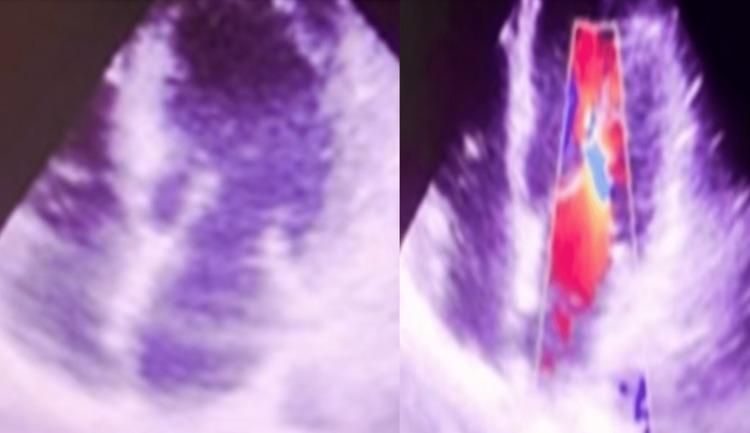

Scorpion stings are painful but harmless and are rarely life-threatening. There is emerging evidence of the association of electrocardiographic (ECG) changes in patients following scorpion stings. We report a case of scorpion sting in a patient in central rural India and provide a review of similar published cases. A 55-year-old previously healthy female was hospitalized in the department of medicine at our institute within two hours of a scorpion sting. She presented with severe pain at the site of the sting and profuse sweating. Her routine investigations (complete blood count renal function test, liver function tests, and arterial blood gas analysis) results were normal. Her electrocardiogram revealed acute myocardial infarction, and serial ECG showed ST and T-wave changes. On laboratory investigation, it was found that her troponin-T was positive and creatinine phosphokinase levels were raised. There was apical wall hypokinesia on transthoracic echocardiography on Day 1 and Day 2. The patient recovered completely and was discharged within five days of hospitalization once her symptoms improved. This case highlights the severe presentation of scorpion stings in otherwise healthy females. The chances of improved clinical symptoms are more if prazosin (125-250 ug) is administered early after scorpion-stung patients experience cardiac abnormalities. This treatment can dramatically alter scorpion envenomation's morbidity and mortality depending on the duration after which it is administered. This case raised our interest due to cardiovascular manifestations in the patient and the early treatment with prazosin for the scorpion sting. Hence, this case was reported for the purpose of creating awareness among physicians and protecting the more vulnerable population.

蝎子蜇伤虽会引起疼痛,但通常无害,很少危及生命。越来越多的证据表明,蝎子蜇伤患者会出现心电图(ECG)变化。我们报告了一例印度中部农村地区患者的蝎子蜇伤病例,并对已发表的类似病例进行了综述。一名55岁、此前健康的女性在被蝎子蜇伤后两小时内被收治于我院内科。她蜇伤部位剧痛且大汗淋漓。其常规检查(全血细胞计数、肾功能检查、肝功能检查和动脉血气分析)结果均正常。她的心电图显示急性心肌梗死,系列心电图显示ST段和T波改变。实验室检查发现她的肌钙蛋白T呈阳性,肌酸磷酸激酶水平升高。第1天和第2天经胸超声心动图显示心尖壁运动减弱。患者完全康复,症状改善后在住院五天内出院。该病例突出了蝎子蜇伤在原本健康女性中的严重表现。如果在蝎子蜇伤患者出现心脏异常后早期给予哌唑嗪(125 - 250微克),临床症状改善的可能性更大。这种治疗可根据给药时间显著改变蝎子蜇伤的发病率和死亡率。由于该患者的心血管表现以及早期使用哌唑嗪治疗蝎子蜇伤,此病例引起了我们的关注。因此,报告该病例旨在提高医生的认识并保护更易受影响的人群。